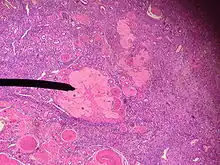

Corps blanc (ou corpus albicans en latin), dans un ovaire de femelle de l'homme, coloration hématoxyline-éosine ou apparenté. On remarque le stroma (Tissu conjonctif cellulaire) à l'aspect "en tourbillon".

Ovaire avec un corps jaune dans la partie supérieure gauche de l'image; et un corps blanc dans sa partie inférieure droite (confer description).